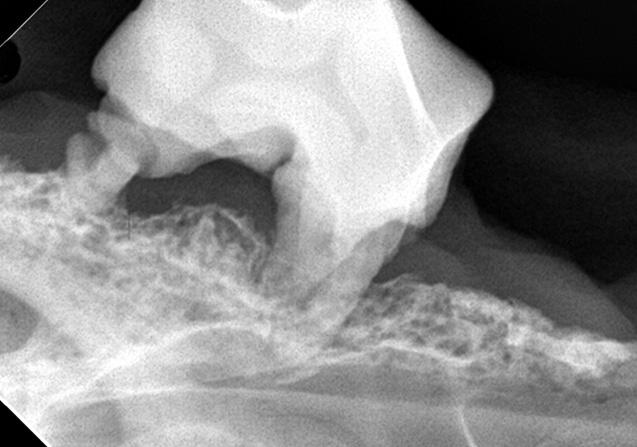

下あご内の、歯を支える骨が溶けている状態(写真提供:かまくらげんき動物病院)